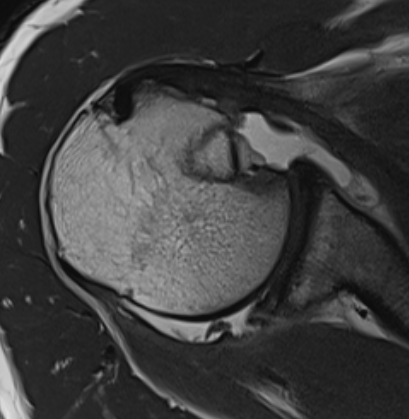

MRI

Acute MRI demonstrating reverse Hill Sachs and posterior labral tear